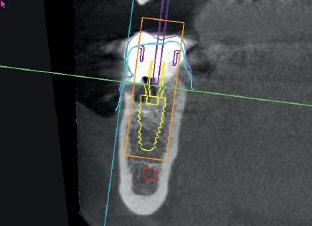

Synergy, as defined by the Cambridge Dictionary, is ‘the combined power of a group of things when they are working together that is greater than the total power achieved by each working separately’. When carrying out surgical procedures it is important that you use equipment solutions developed to offer a synergistic approach to your surgical processes. The equipment and instruments used should work in harmony to allow you to provide top quality treatment.

When it comes to synergy in dental implant procedures, such an approach often enables dental professionals to achieve better accuracy during the surgical phase. For instance, guided implant surgery utilises computer-generated surgical guides to enhance the precision of implant placement. By combining 3D imaging technology with specialised surgical instruments, dental clinicians are able to carefully plan the position, angle, and depth of the dental implant prior to the actual surgery. This collaborative effort between advanced imaging software and specialised instruments ensures that the implant is placed precisely in the desired location, leading to better aesthetic outcomes and increased patient satisfaction.

Seamless integration

Another advantage of instrument synergy in dental implant procedures is the reduced risk of surgical complications. Using specially designed surgical instrument and handpieces, allow dentists to ensure that they have everything necessary and readily available during a procedure. This allows the dental team to work efficiently and

effectively. The benefits of using compatible handpieces and equipment ensures that they can be seamlessly integrated into the surgical workflow, further reducing the time required for the procedure.

Seamless integration of instruments in dental implant procedures can also improve patient comfort and reduce recovery time. Advanced technology, such as piezoelectric instruments using ultrasound technology, offers precise and controlled cutting of bone, minimising trauma to the surrounding tissues. This means that patients experience less pain, swelling and bruising post-surgery, leading to a quicker and more comfortable recovery. Additionally, the combined use of specialised instruments, such as tissue punches and implant placement tools, allows for minimally invasive techniques that preserve the integrity of soft tissues. By reducing damage to the surrounding structures, patients experience less post-operative discomfort and achieve quicker healing.